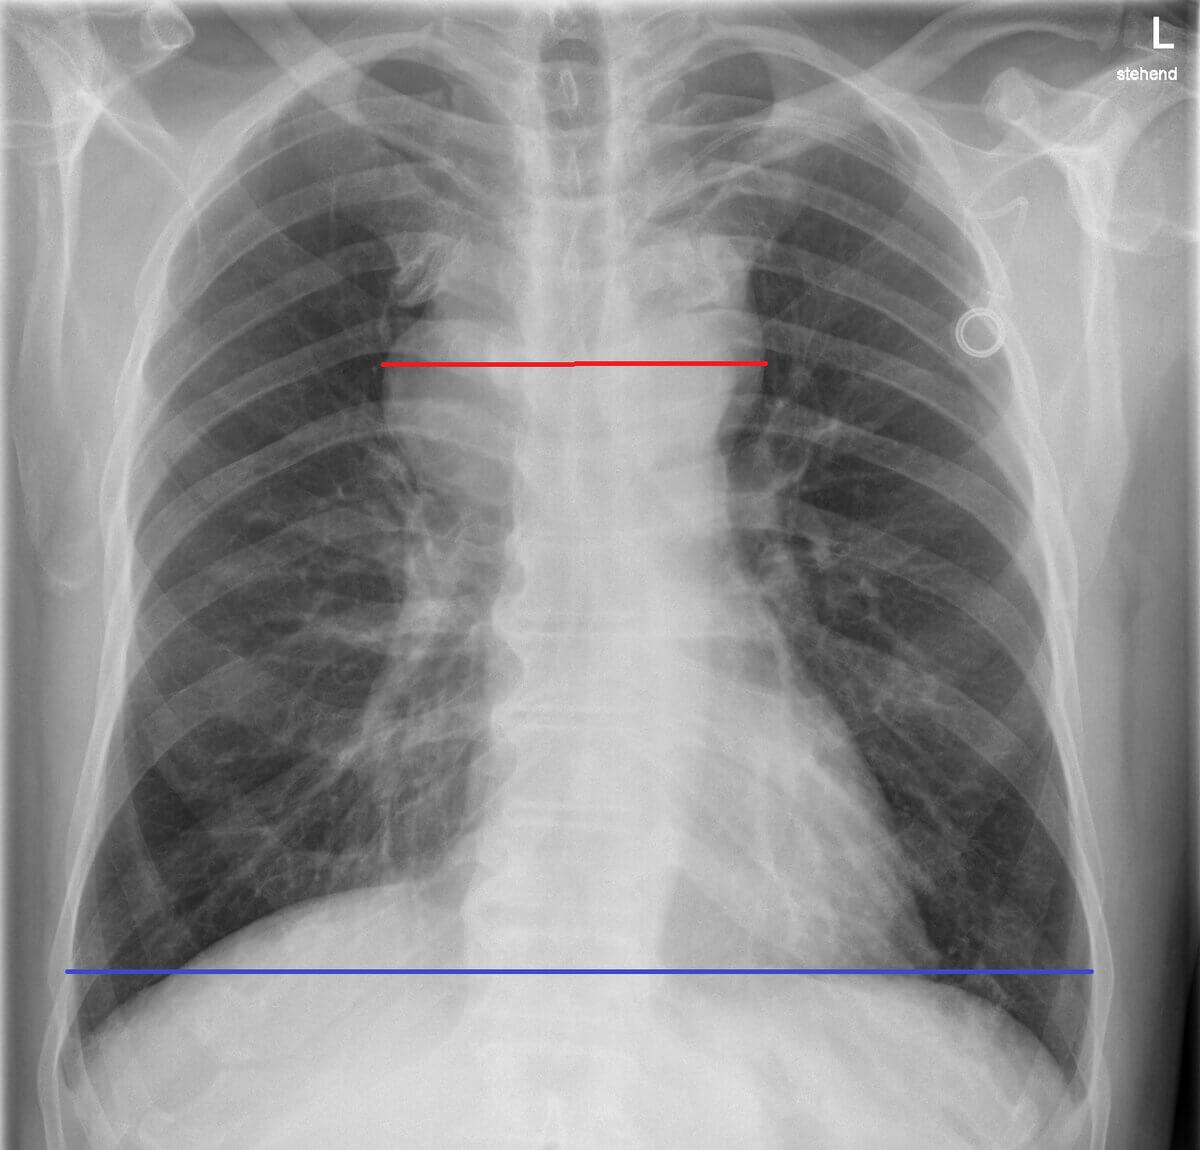

- Röntgen-Thorax: p.a.-Aufnahme zum Ausschluss eines großen Mediastinaltumors

- großer Mediastinaltumor (mind. 1/3 des maximalen Thoraxquerdurchmessers im p.a.-Röntgen-Thorax)

- Bildquelle DICOM-Viewer: Idris et al (2024). Mediastinal Lymph Node Quantification (LNQ): Segmentation of Heterogeneous CT Data (Version 1) case_0064. The Cancer Imaging Archive